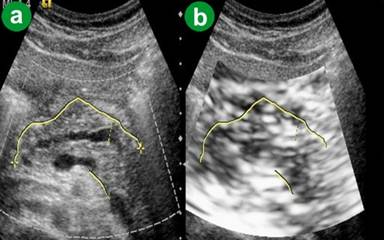

The ARFI-VTQ values for the pancreatic parenchyma ranged from 0.65 m/s to 1.74 m/s with a mean value of 1.240±0.235 m/s (Table 2; Figure 1). On eSie touch elastogram the pancreatic parenchyma and peripheral fat appeared light gray to gray (scores 2-3) on gray scale (Figure 3), while on the color scale it was yellowish green to yellow (scores 2-3; Figure 4).

Figure 3. Chronic pancreatitis. a. US B-mode image. b. eSie touch gray scale image (light gray to gray: score 2-3). |

Figure 4. Chronic pancreatitis. a. US B-mode image. b. eSie touch color scale image (yellowish green to yellow: score 2-3). |